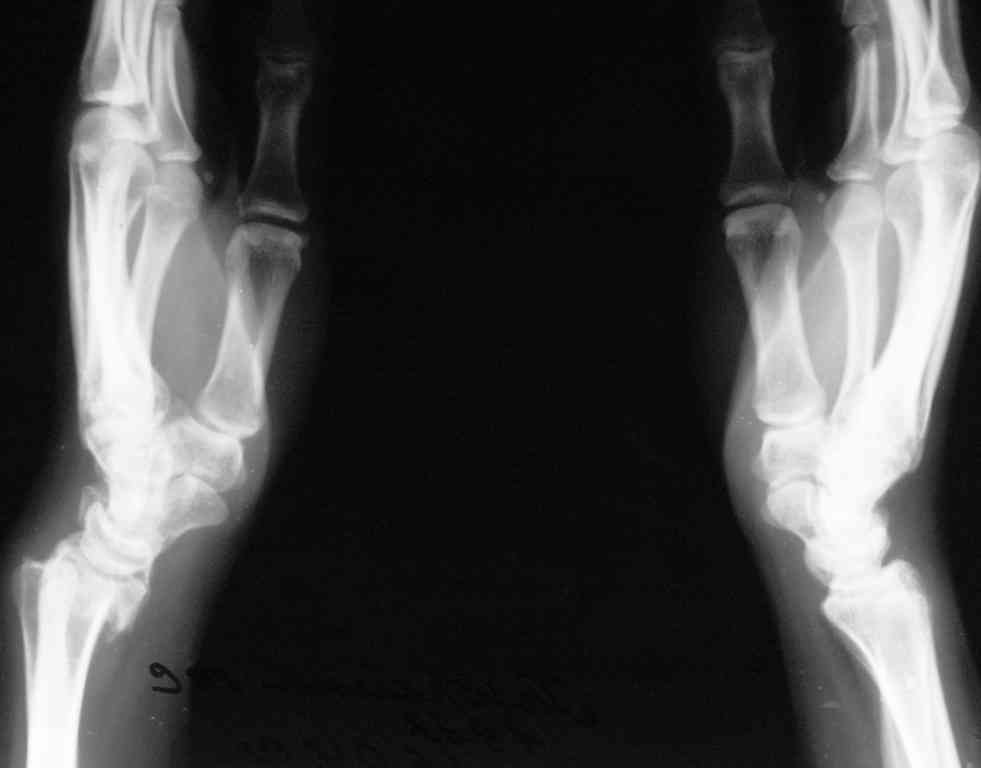

Судя по показанным Рг граммам, очевиден посттравм. артроз лучезапястного сустава, проблема дистального радиоульнарного сочленения(TFCC).

Угол наклона лучевой фасетки в норме в пределах 10-15 градусов, на представленном боковом снимке -может быть чуть больше 15градусов. Выполнив

разгибательную остеотомию луча, ты поставишь фасетку в нейтральное положение и таким образом увеличится угол разгибания , но уменьшится сгибание. По сути, амплитуда движений останется такой же.

Первым этапом я бы убрал пластину с последующей ограниченной резекцией головки локтевой кости(hemiresection and interposition arthroplasty Bowers technique). провести курс реабилитации. если уровень мобильности сустава не

будет устраивать больного, можно рассмотреть проксимальную карпальную резекцию в качестве последующего этапа.

При наличии пронационной контрактуры (которая скорее всего и доминирует в его жалобах) и несращения локтевой кости в таком месте, операция Суав-Капанджи напрашивается сама собой.